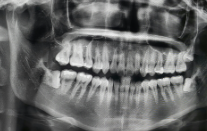

사랑니 발치 수술은 일반적으로 치과에서 시행되며, 수술 전에는 환자의 전반적인 건강 상태와 사랑니의 위치, 크기, 형태 등을 평가하기 위해 X선 촬영을 시행합니다. 수술 당일, 환자는 마취제를 투여받고, 치과 의사는 주변 부위를 굳혀주기 위해 약간의 직접 마사지를 하거나 냉동 마취를 시행합니다. 이후에 치과 의사는 소형 송곳이나 철사로 잇몸을 개방하고, 사랑니를 조심스럽게 제거합니다.